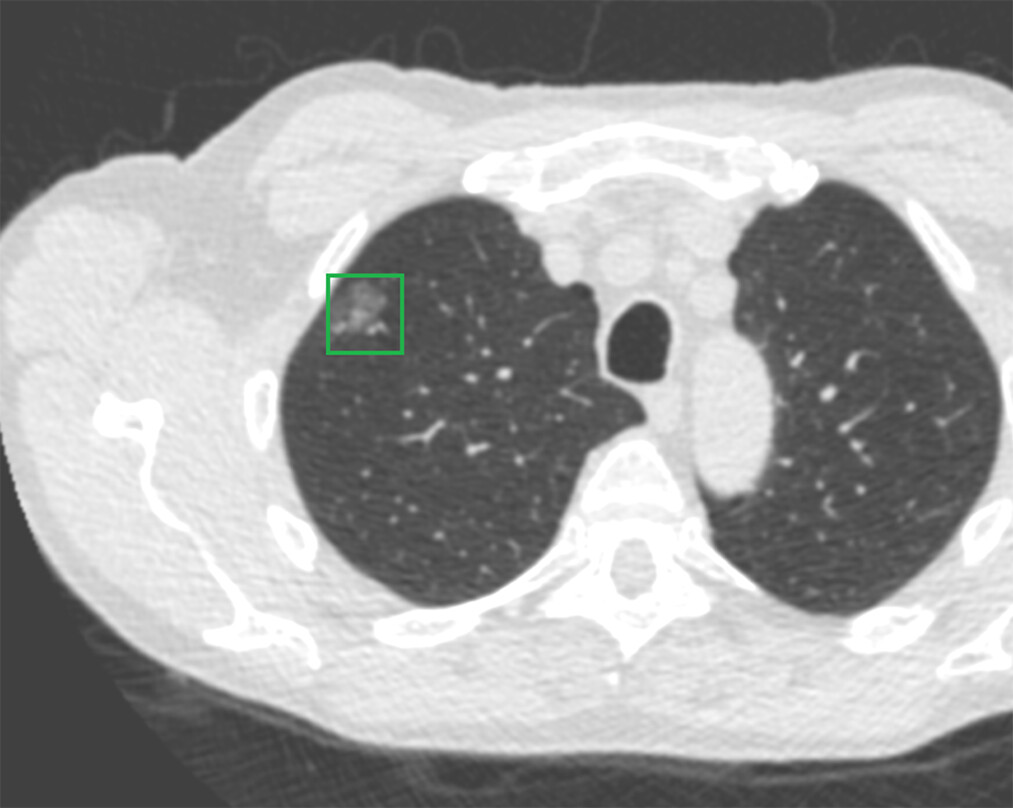

低線量肺CT診断画像1

低線量肺CT診断画像2

低線量肺CT診断画像3

低線量肺CT検査

低線量肺CT検査は、通常のCT検査よりも少ない放射線量で肺の状態を詳しく調べる検査です。

胸部X線検査よりも小さな病変の発見に優れており、肺がんの早期発見に役立ちます。

この検査でわかること

• 肺がんの疑い

• 慢性閉塞性肺疾患(COPD)などの肺の病気

• 肺の結節影などの所見

• 肺の炎症や過去の病変の痕跡